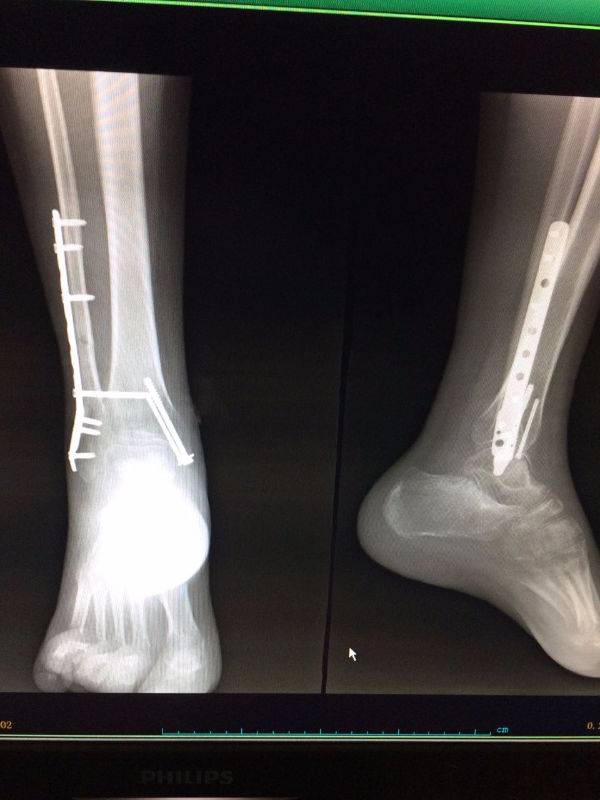

手术非常好,顺便请教一下。患者.男,25岁,右腓骨下段及内踝骨折,切开复位内固定术后120天,外踝部钢板外露,半月前行扩创缝合,目前仍未完全愈合,伴少量渗出,踝关节功能僵硬。请教治疗方案。谢谢

mmexport1496478329835.jpg